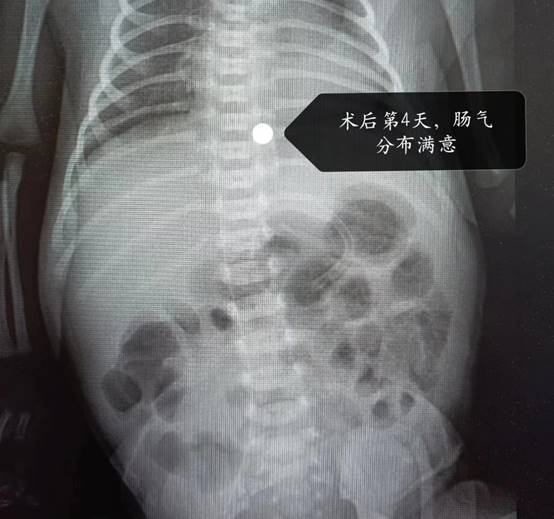

术后4天,宝宝顺利排出了肠管吻合后的第一次墨绿色胎便,复查腹部立位片看到肠管充气满意,家属得知宝宝恢复情况良好,激动的向曹振杰主任再次表达了诚挚的感谢!